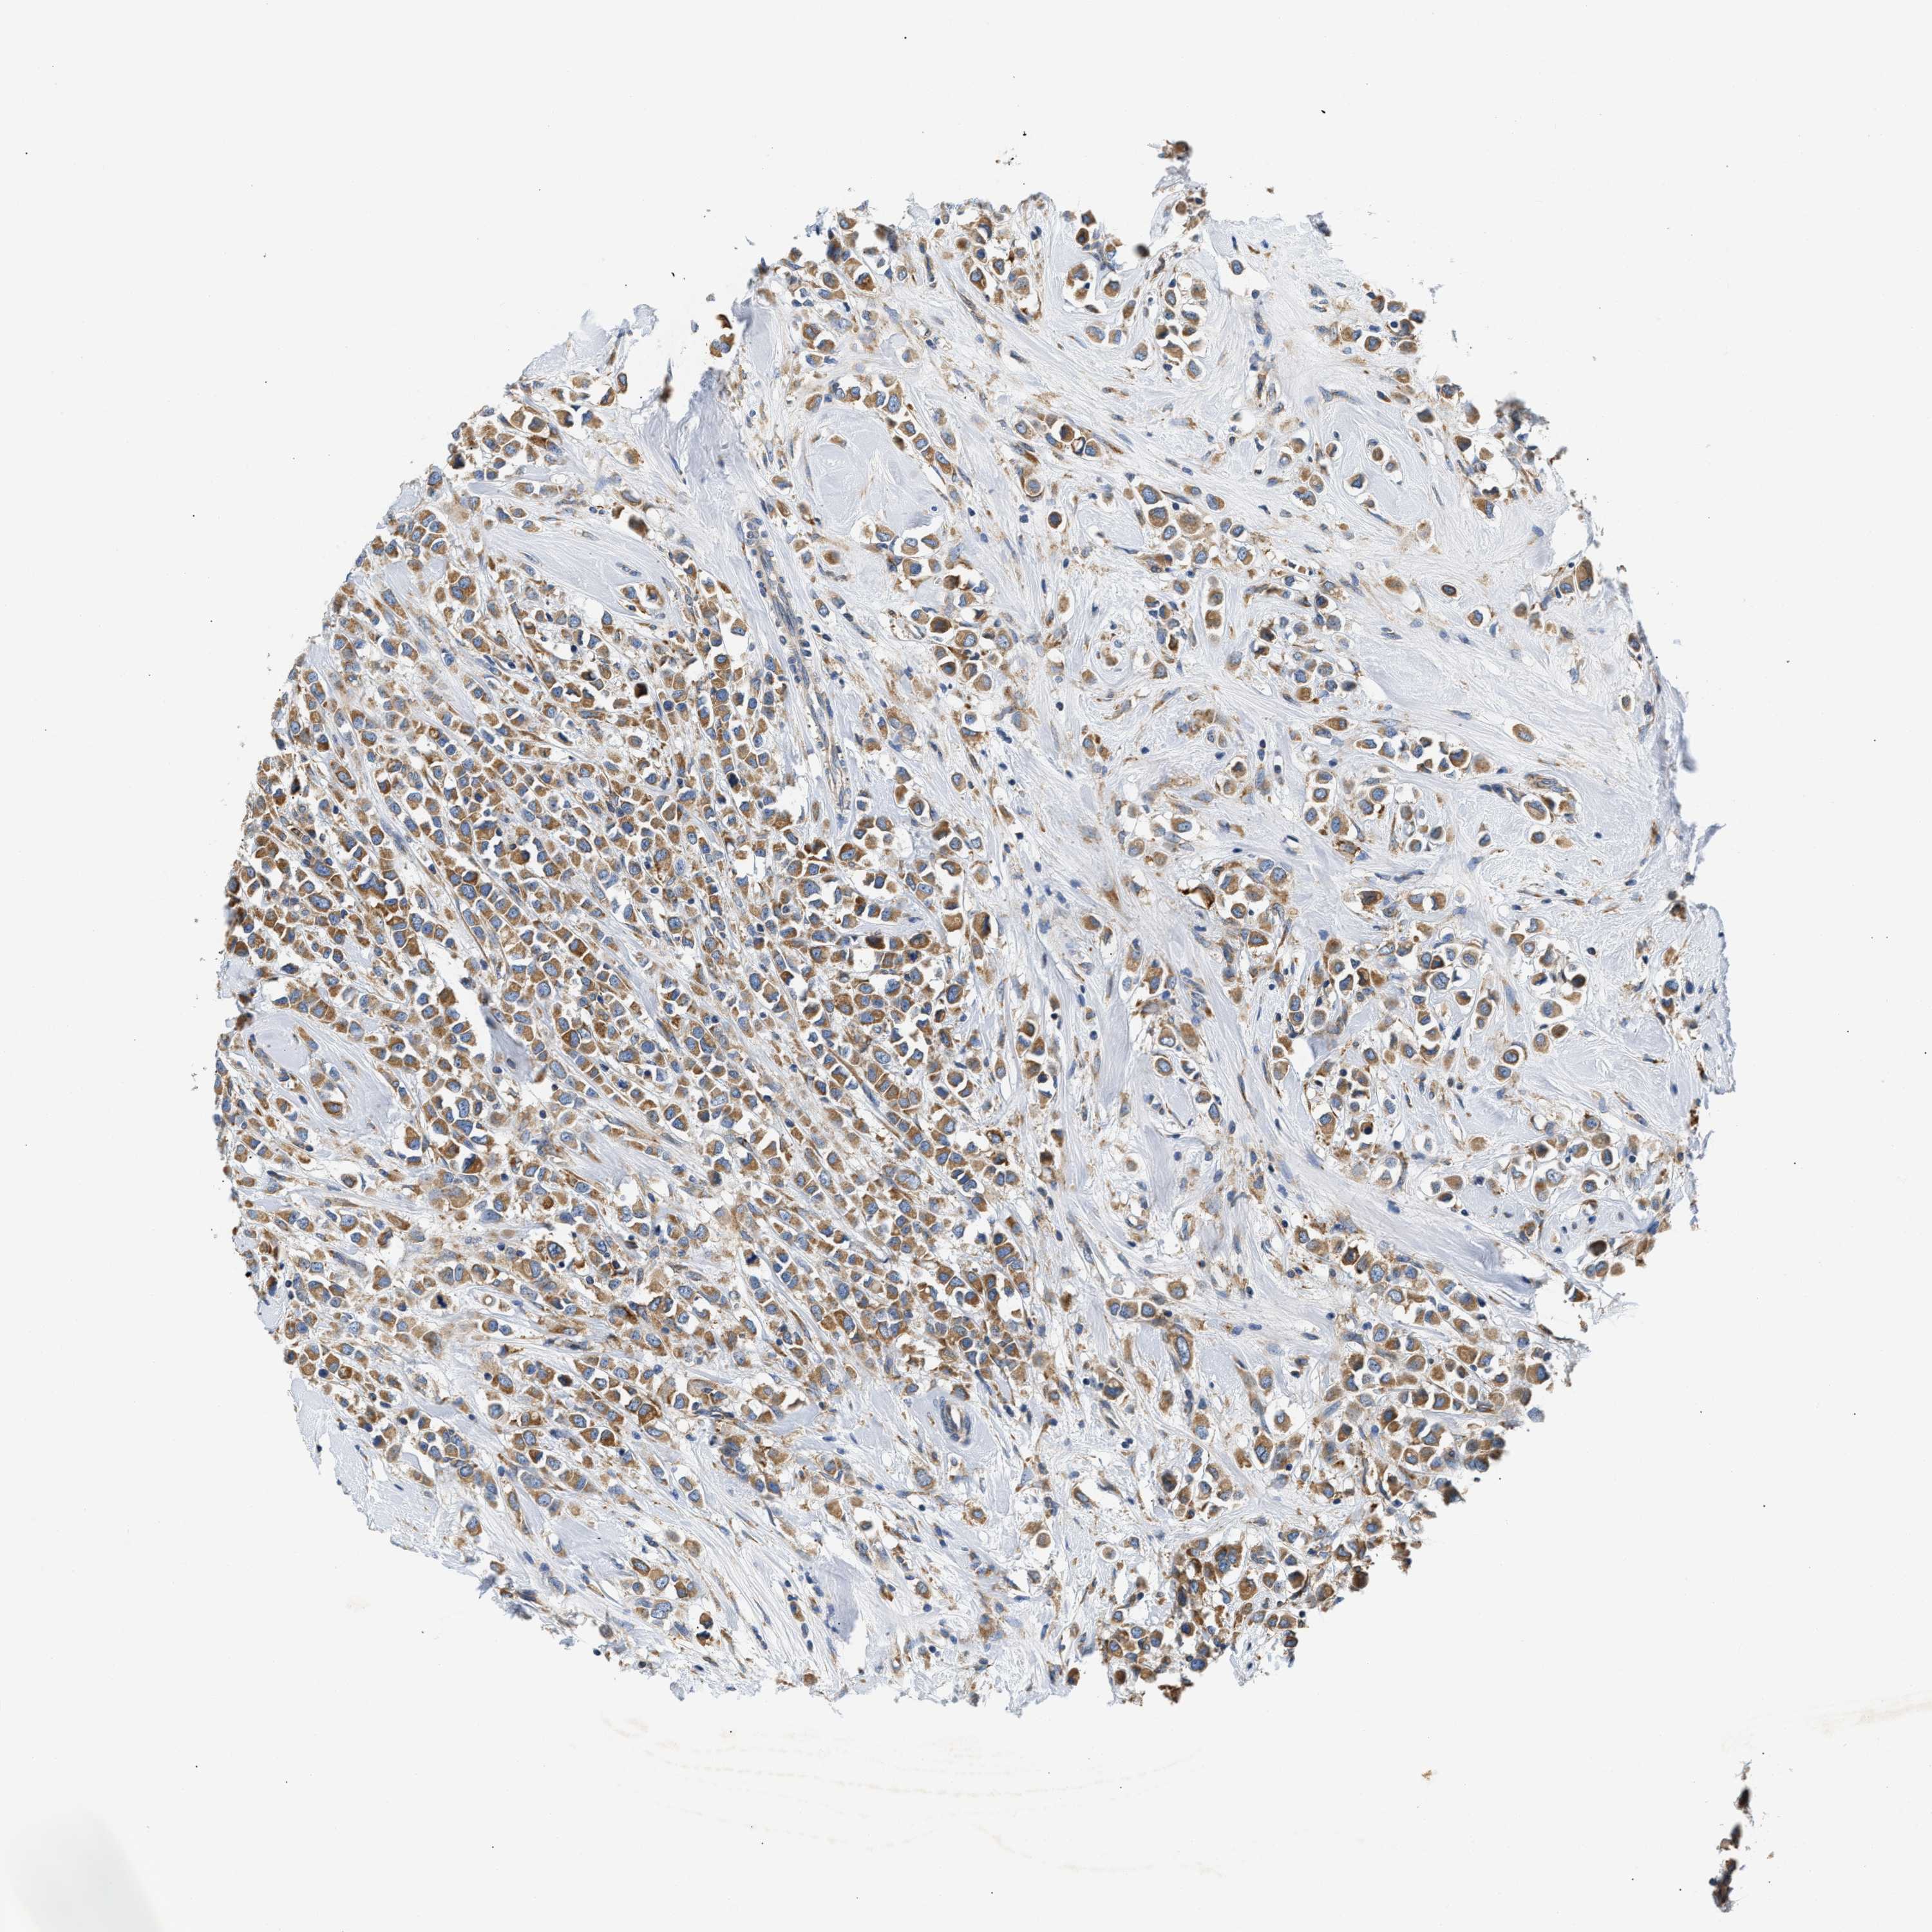

CANCER BREAST CANCER Show tissue menu

BRCA TCGA BRCA VALIDATION PROTEIN EXPRESSION